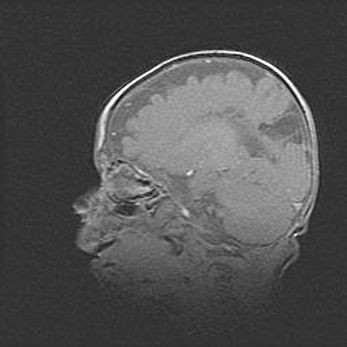

Наружная гидроцефалия с возможной атрофией височных областей.

Возраст: 28 дней

Вес: 3670 г

Пол: мужской

Окружность головы: 38 см

Срок гестации: 40 недель

Гидроцефалия головного мозга у новорожденных – это заболевание, которое характеризуется скоплением избыточного количества спинномозговой жидкости в желудочковой системе головного мозга в результате затруднения её перемещения от места выработки к месту поглощения в кровеносную систему или вследствие нарушения абсорбции. При открытой наружной форме гидроцефалии у новорожденных расширяются и переполняются субарахноидные пространства.

При нормотензивных  формах,  которые,  как  правило,  являются  следствием  перенесенных ишемических  повреждений  паренхимы  мозга,  возможно  сочетание микроцефалии  с нормотензивной гидроцефалией. В основе данных изменений лежит атрофия больших полушарий с преимущественной  локализацией  в  лобно-височных  областях.